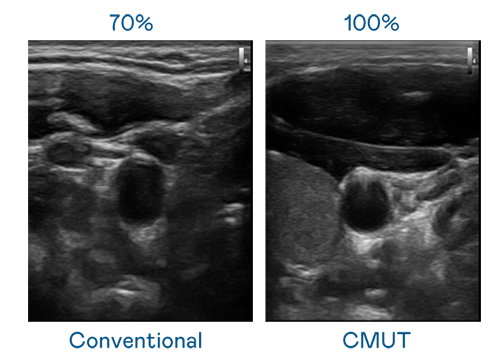

CMUT 技术是一种用电容式微机电元件来产生超音波讯号的技术。与传统 PZT 压电式技术相比,CMUT 频宽增加 30%,更宽频的超音波讯号让影像解析度大幅提升,是实现高影像品质医疗超音波扫描、促进精准医疗发展的关键技术。

超音波影像的解析度高低,首先取决于探头能发出的讯号频宽。雷火竞技 CMUT 可提供高清晰的超音波讯号,提供高频宽、高灵敏度、影像纹理细节更高的超音波影像,协助医护人员缩短影像判读时间及利用精准的医疗影像进行诊断。